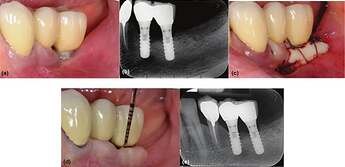

Clinical (a) and radiographic (b) views of the distal implant in region 3.6, placed 8 years earlier, demonstrate the lack of keratinized tissue (KT), peri‐implant soft‐tissue recession, and plaque accumulation. A free gingival graft (FGG) was performed to enhance the peri‐implant soft‐tissue conditions (c). Clinical (d) and radiographic (e) evaluations at the 20‐year follow‐up reveal minimal peri‐implant probing pocket depth, no bleeding on probing, and stable peri‐implant soft‐tissue conditions.